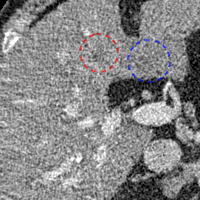

To show the denoising effect of the selected networks, we took two representative slices as shown in Figs. 5 and 7. And Figs. 6 and 8 are the zoomed regions-of-interest (ROIs) marked by the red rectangles in Figs. 5 and 7. All the networks demonstrated certain denoising capabilities. However, CNN-MSE blurred the images and introduced waxy artifacts as expected, which are easily observed in the zoomed ROIs in Figs. 6e and 8e. WGAN-MSE was able to improve the result of CNN-MSE by avoiding over-smooth but minor streak artifacts can still be observed especially compared to CNN-VGG and WGAN-VGG. Meanwhile, using WGAN or GAN alone generated stronger noise (Figs. 6g and 8g) than the other networks enhanced a few white structures in the WGAN/GAN generated images, which are originated from the low dose streak artifact in LDCT images, while on the contrary the CNN-VGG and WGAN-VGG images are visually more similar to the NDCT images. This is because the VGG loss used in CNN-VGG and WGAN-VGG is computed in a feature space that is trained previously on a very large natural image dataset [48]. By using VGG loss, we transferred the knowledge of human perception that is embedded in VGG network to CT image quality evaluation. The performance of using WGAN or GAN alone is not acceptable because it only maps the data distribution from LDCT to NDCT but does not guarantee the image content correspondence. As for the lesion detection in these two slices, all the networks enhance the lesion visibility compared to the original noisy low dose FBP images as noise is reduced by the different approaches.

As for iterative reconstruction technique, the reconstruction results depend greatly on the choices of the regularization parameters. The implemented dictionary learning reconstruction (DictRecon) result gave the most aggressive noise reduction effect compared to the network outputs as a result of strong regularization. However, it over-smoothed some fine structures. For example, in Fig. 8, the vessel pointed by the green arrow was smeared out while it is easily identifiable in NDCT as well as WGAN-VGG images. Yet, as an iterative reconstruction method, DictRecon has its advantage over post-processing method. As pointed by the red arrow in Fig 8, there is a bright spot which can be seen in DictRecon and NDCT images, but is not observable in LDCT and network processed images. Since the WGAN-VGG image is generated from LDCT image, in which this bright spot is not easily observed, it is reasonable that we do not see the bright spot in the images processed by neural networks. In other words, we do not want the network to generate structure that does not exist in the original images. In short, the proposed WGAN-VGG network is a post-processing method and information that is lost during the FBP reconstruction cannot easily be recovered, which is one limitation for all the post-processing methods. On the other hand, as an iterative reconstruction method, DictRecon algorithm generates images from raw data, which has more information than the post-processing methods.